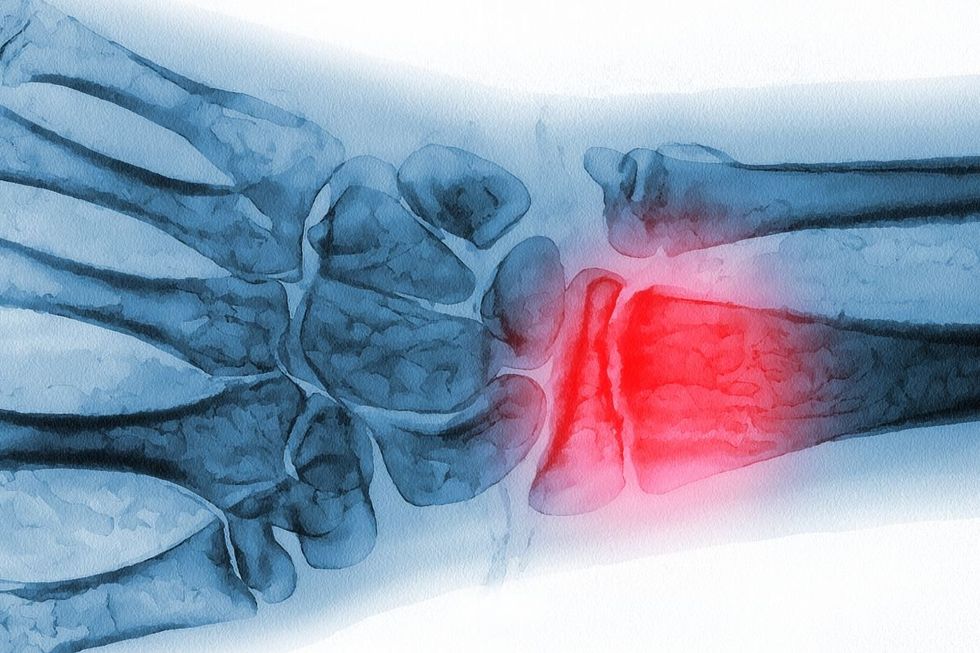

It comes as around 3.5 million people across the UK are thought to be living with osteoporosis, yet many don’t realise they could be affected until it’s too late.

Everyday habits might be putting our bones at risk